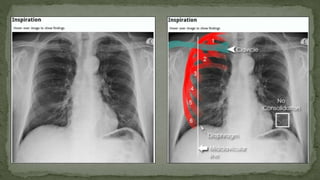

F. Inspiration (Degree of inspiration)

 To judge the degree of inspiration, count the number of ribs above the

diaphragm.

 The midpoint of the right hemi-diaphragm should be between the 5th and 7th

ribs anteriorly.

 The anterior end of the 6th rib should be above the diaphragm as should the

posterior end of the 10th rib.

 If more ribs are visible the patient is hyperinflated

 If fewer it indicates inadequate inspiration

 Poor inspiration will make the heart look larger, give appearance of basal

shadowing and cause the trachea to appear deviated to the right